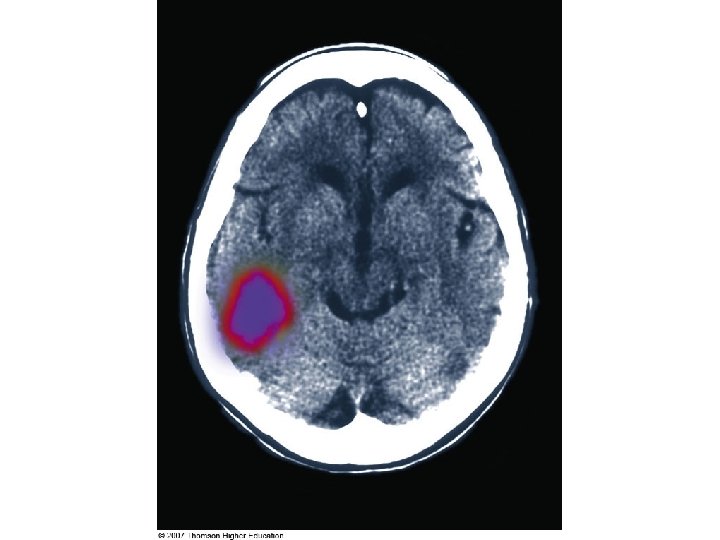

Neurological Disorders Stroke – disruption of brain function d/t blockage or interruption of blood flow ◦ Ischemic stroke ◦ Hemorrhagic stroke ◦ TIA ◦ Aneurysm

Neurological Disorders Stroke ◦ Signs/symptoms Loss of vision or speech, paralysis, muscle weakness, change in mental status ◦ Diagnosis National Institutes of Health Stroke Scale CT, MRI, PET imaging